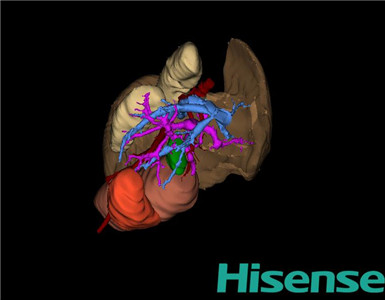

将0.625mm双源薄层CT资料的静脉期和动脉期Dicom格式文件导入海信CAS系统。

通过调节窗宽窗位调整CT序号,对肿瘤,肝实质,胆囊,下腔静脉,肿瘤,肝动脉、门静脉及肝静脉等进行三维重建;系统自动计算肿瘤体积和肝脏体积。

模拟手术操作,自动计算切除肿瘤体积。三维可见肿瘤来源于膀胱,需将部分膀胱切除。

术前三维重建:

重建图片